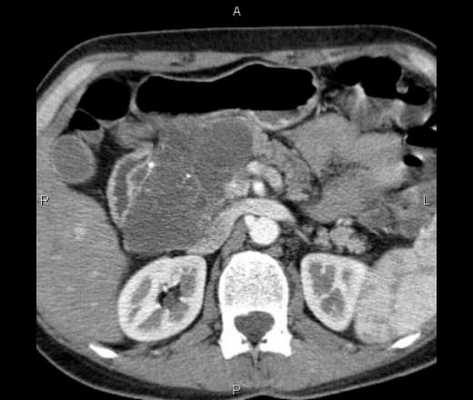

В ходе недавней колоноскопии обнаружено подслизистое новообразование размером около 2 см в восходящей ободочной кишке, которое посчитали липомой (рис. 1, 2). РКТ показала опухоль в восходящем отделе ободочной кишки, исходящую из ее боковой стенки, — размером 12 мм и округлой формы. При этом отмечено накопление опухолью контраста (рис. 3-5). Лимфаденопатии не зафиксировано.